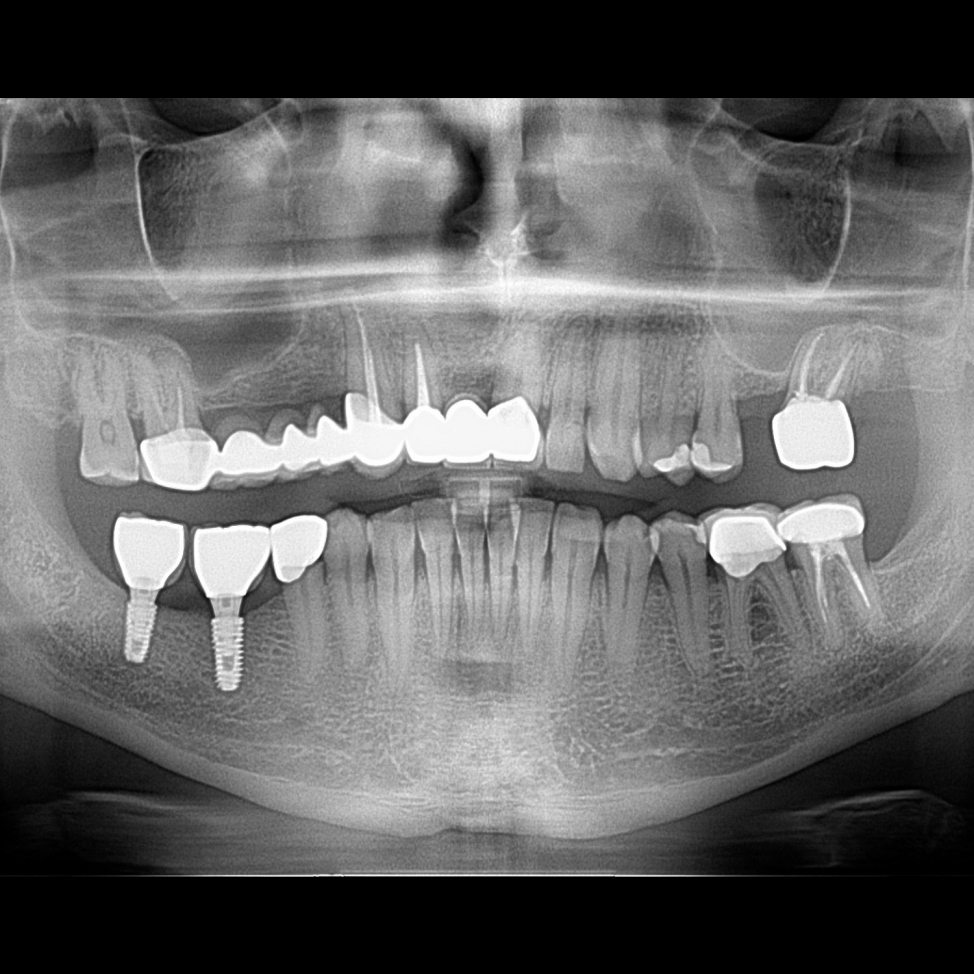

İmplant etrafındaki kemik açıklığını kemik grefti ile tedavi ettiğimiz vakamız.